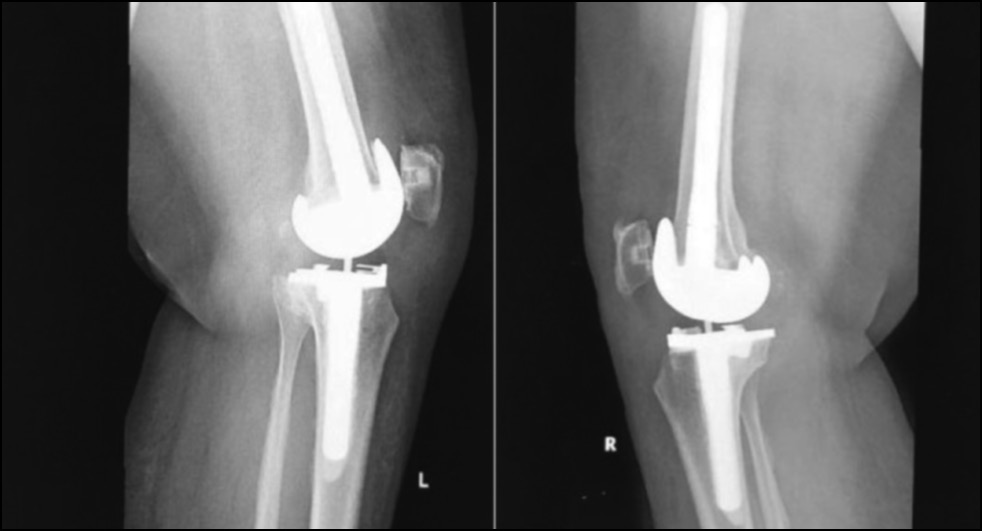

CASE 4. PATIENT 25

Age: 65 years.

Sex: Male.

Diagnosis: Bilateral advanced knee osteoarthritis.

Procedure: Bilateral simultaneous knee arthroplasty.

Associated illnesses: No associated comorbidities.

Postoperative follow-up: No postoperative complications were encountered.

Length of hospital stay: 6 days.

Radiological assessment (Fig. 23–26)

Fig. 25. Ap postoperative x-ray showing bilateral total knee arthroplasty.

Рис. 25. Послеоперационная рентгенограмма с двусторонней тотальной артропластикой коленного сустава.

Fig. 26. Lateral postoperative x-ray right and left knees showing bilateral total knee arthroplasty.

Рис. 26. Послеоперационная боковая рентгенограмма правого и левого колена, демонстрирующая двустороннюю тотальную артропластику коленного сустава.